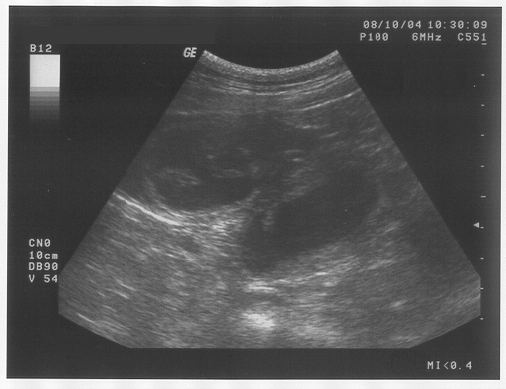

Er hat mir noch mal diesen Glibberkram auf den Bauch geschmiert und dann haben alle ganz fasziniert auf eine Art Fernseher geschaut. Da kam aber weder "Herrchen gesucht" noch Werbung. Eigentlich hab ich da gar nichts erkennen können.

Nur der Mann und Frauchen und Brigitte, die haben sich gefreut und gemeint, dass es wohl wieder mindestens 6 Babies geben wird. Vielleicht sogar mehr. Ich hab euch die Bilder mal mitgebracht - vielleicht könnt ihr ja was entdecken. Für mich sieht das eher aus wie Seifenblasen.